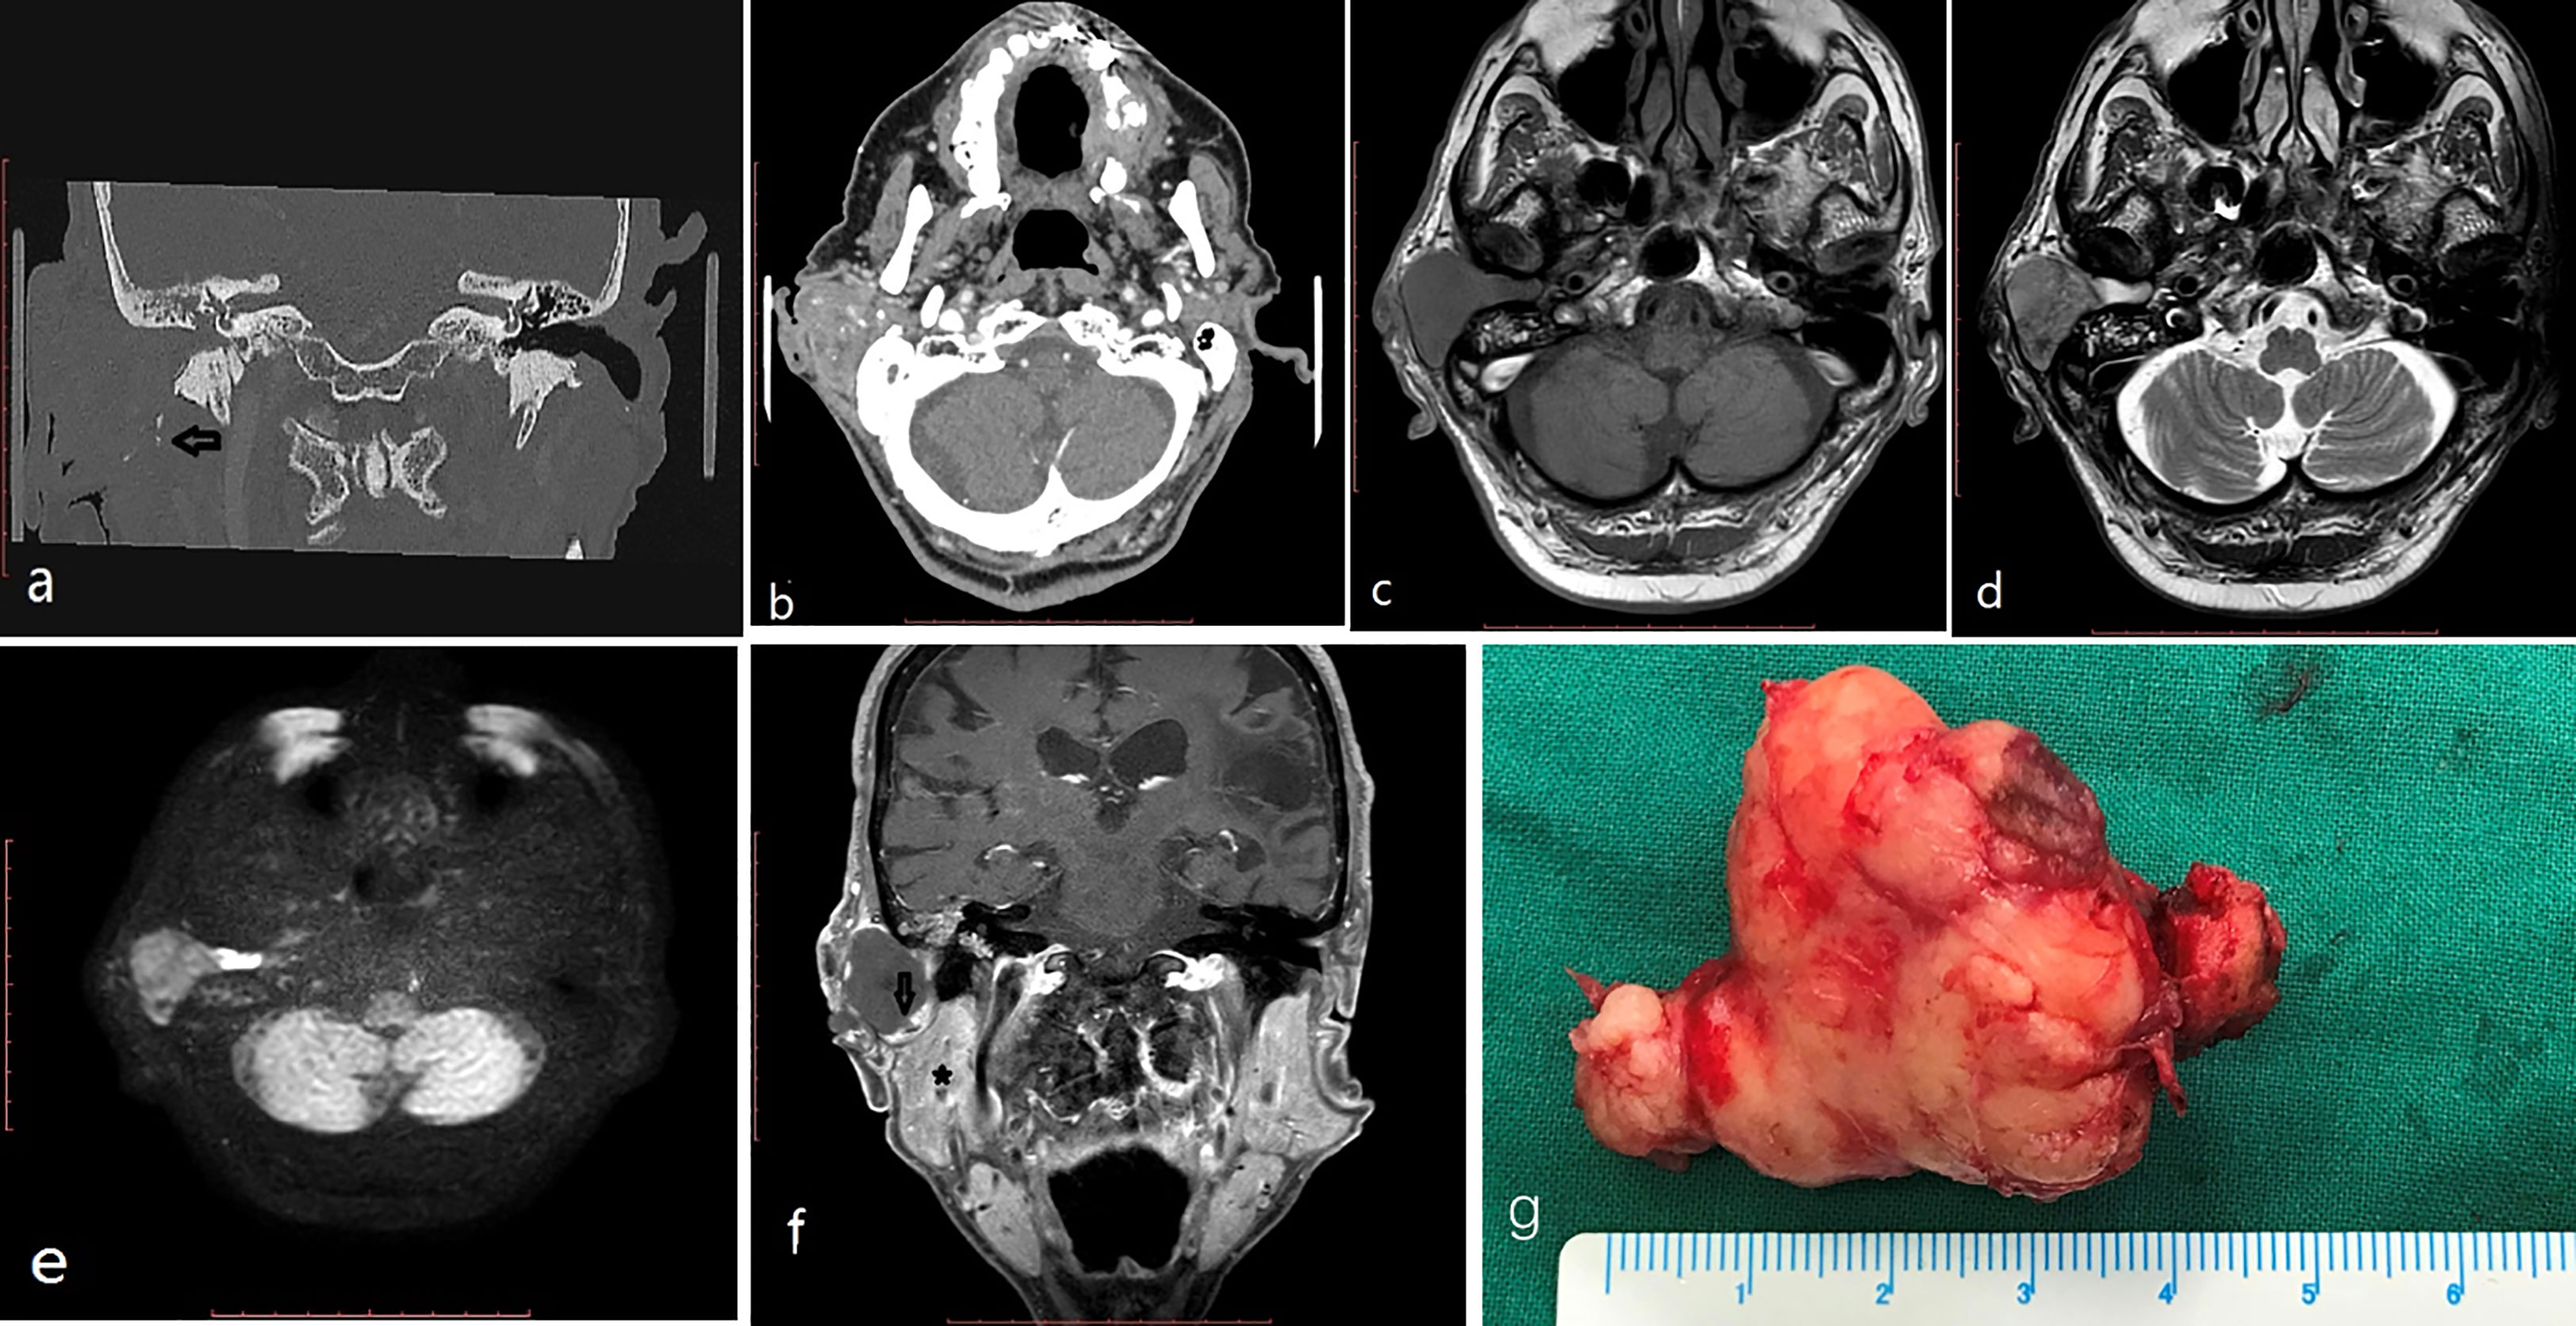

Figure 2 (case 8) An 84-year-old man had a 36mm max diameter ceruminous pleomorphic adenoma in the right EAC protruding out from the EAC and extending to the parotid (behind the mass, cholesteatoma was found in the EAC). CT: (A, B) calcified foci (black arrow) and heterogenous enhancement in the tumor. MRI (C-F):T1 low intensity (C), T2 intermediate and high signal intensity (D), DWI intermediate signal intensity (E) (behind the mass, cholesteatoma appeared as high intensity); the mass showed edge enhancement (black arrow) and was adjacent to the parotid (star) on coronal enhanced T1 (F). The mass is a lobulated solid mass on the gross appearance (G).

On temporal HRCT, all of the lesions exhibited isoattenuating soft tissue masses in the EAC, one mildly involved the tympanic bone (Figure 1). In one patient several calcification foci were found in the mass, and the mass showed heterogenous enhancement on the CT with the soft window. Seven cases were examined with MRI, six cases underwent contrast-enhanced MRI, and DWI was performed in five cases. On T1WI, four cases demonstrated intermediate signal intensity, two cases showed mixture of intermediate and high signal intensity, and one case showed low signal intensity. On T2WI, four cases demonstrated high signal intensity, two cases showed mixture of intermediate and high signal intensity, and one case showed intermediate signal intensity. On contrast-enhancement T1WI, three cases showed edge enhancement, two cases homogenous enhancement, one case heterogenous enhancement. On DWI of five cases, all tumors appeared as intermediate signal intensity, but in two of them high signal intensity of cholesteatoma was also found deep to the tumor in the EAC (Figures 2D, F). Figure 2 showed that the tumor was adjacent to the parotid gland, however, the Figure 2F revealed the tumor was originated in the EAC, there was a gap between the tumor and the parotid gland, and Figure 2G revealed the integrity of the tumor capsule. Thus, the tumor did not contain any salivary gland tissue, and the tumor originated in the EAC (See Table 2).

CT as a routine examination can determine the exact location of the tumor and evaluate whether there is bone destruction or not. On CT examination ceruminous adenomas usually present as a soft mass. In our series there was no tympanic bone destruction in all cases except one case, in which only mild bone destruction was found. Calcification foci were found in one of our cases with ceruminous pleomorphic adenoma (Figures 2A, B). Calcification in ceruminous adenoma was not reported in the literature. The calcification is thought to be a result of long-term tumor progression in pleomorphic adenoma of other sites. The frequency of calcification was 50% in parapharyngeal space pleomorphic adenoma and 15% in parotid pleomorphic adenoma (8, 9).

MRI can determine the extent and margin of the tumor. Ceruminous adenoma usually demonstrated a well-circumicised mass without infiltration to adjacent tissue. In one of our cases the tumor growed adjacent to the parotid but showed no infiltration. They might show intermediate, high or low signal intensity on T1WI, and show intermediate or high signal intensity on T2WI. They may show homogenous, or heterogenous, or edge enhancement. On DWI they showed as intermediate signal, but cholesteatoma behind the tumor appeared as high signal (Figure 2E).